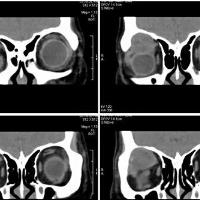

女,54岁,头痛头晕月余,无眼部症状及视力异常。 影像表现:右侧眼球后方占位病变,考虑海绵状血管瘤可能性大,鉴别:视神经鞘瘤、脑膜瘤及炎性假瘤。 病例点评:眼眶内血管瘤是较常见的良性肿瘤,其中以海绵状血管瘤最常见。可发生于任何年龄,主要表现为眼球突出及偏位,在低头或哭泣时可有突眼加重。可经眶缘触及具有压缩性的肿块。视力损害多较缓慢。肿块大多位于肌锥内,其次为肌锥外,平扫呈边界清楚的圆形、卵圆形或分叶状肿块,增强扫描呈缓慢进行性显著强化为其特征性表现。